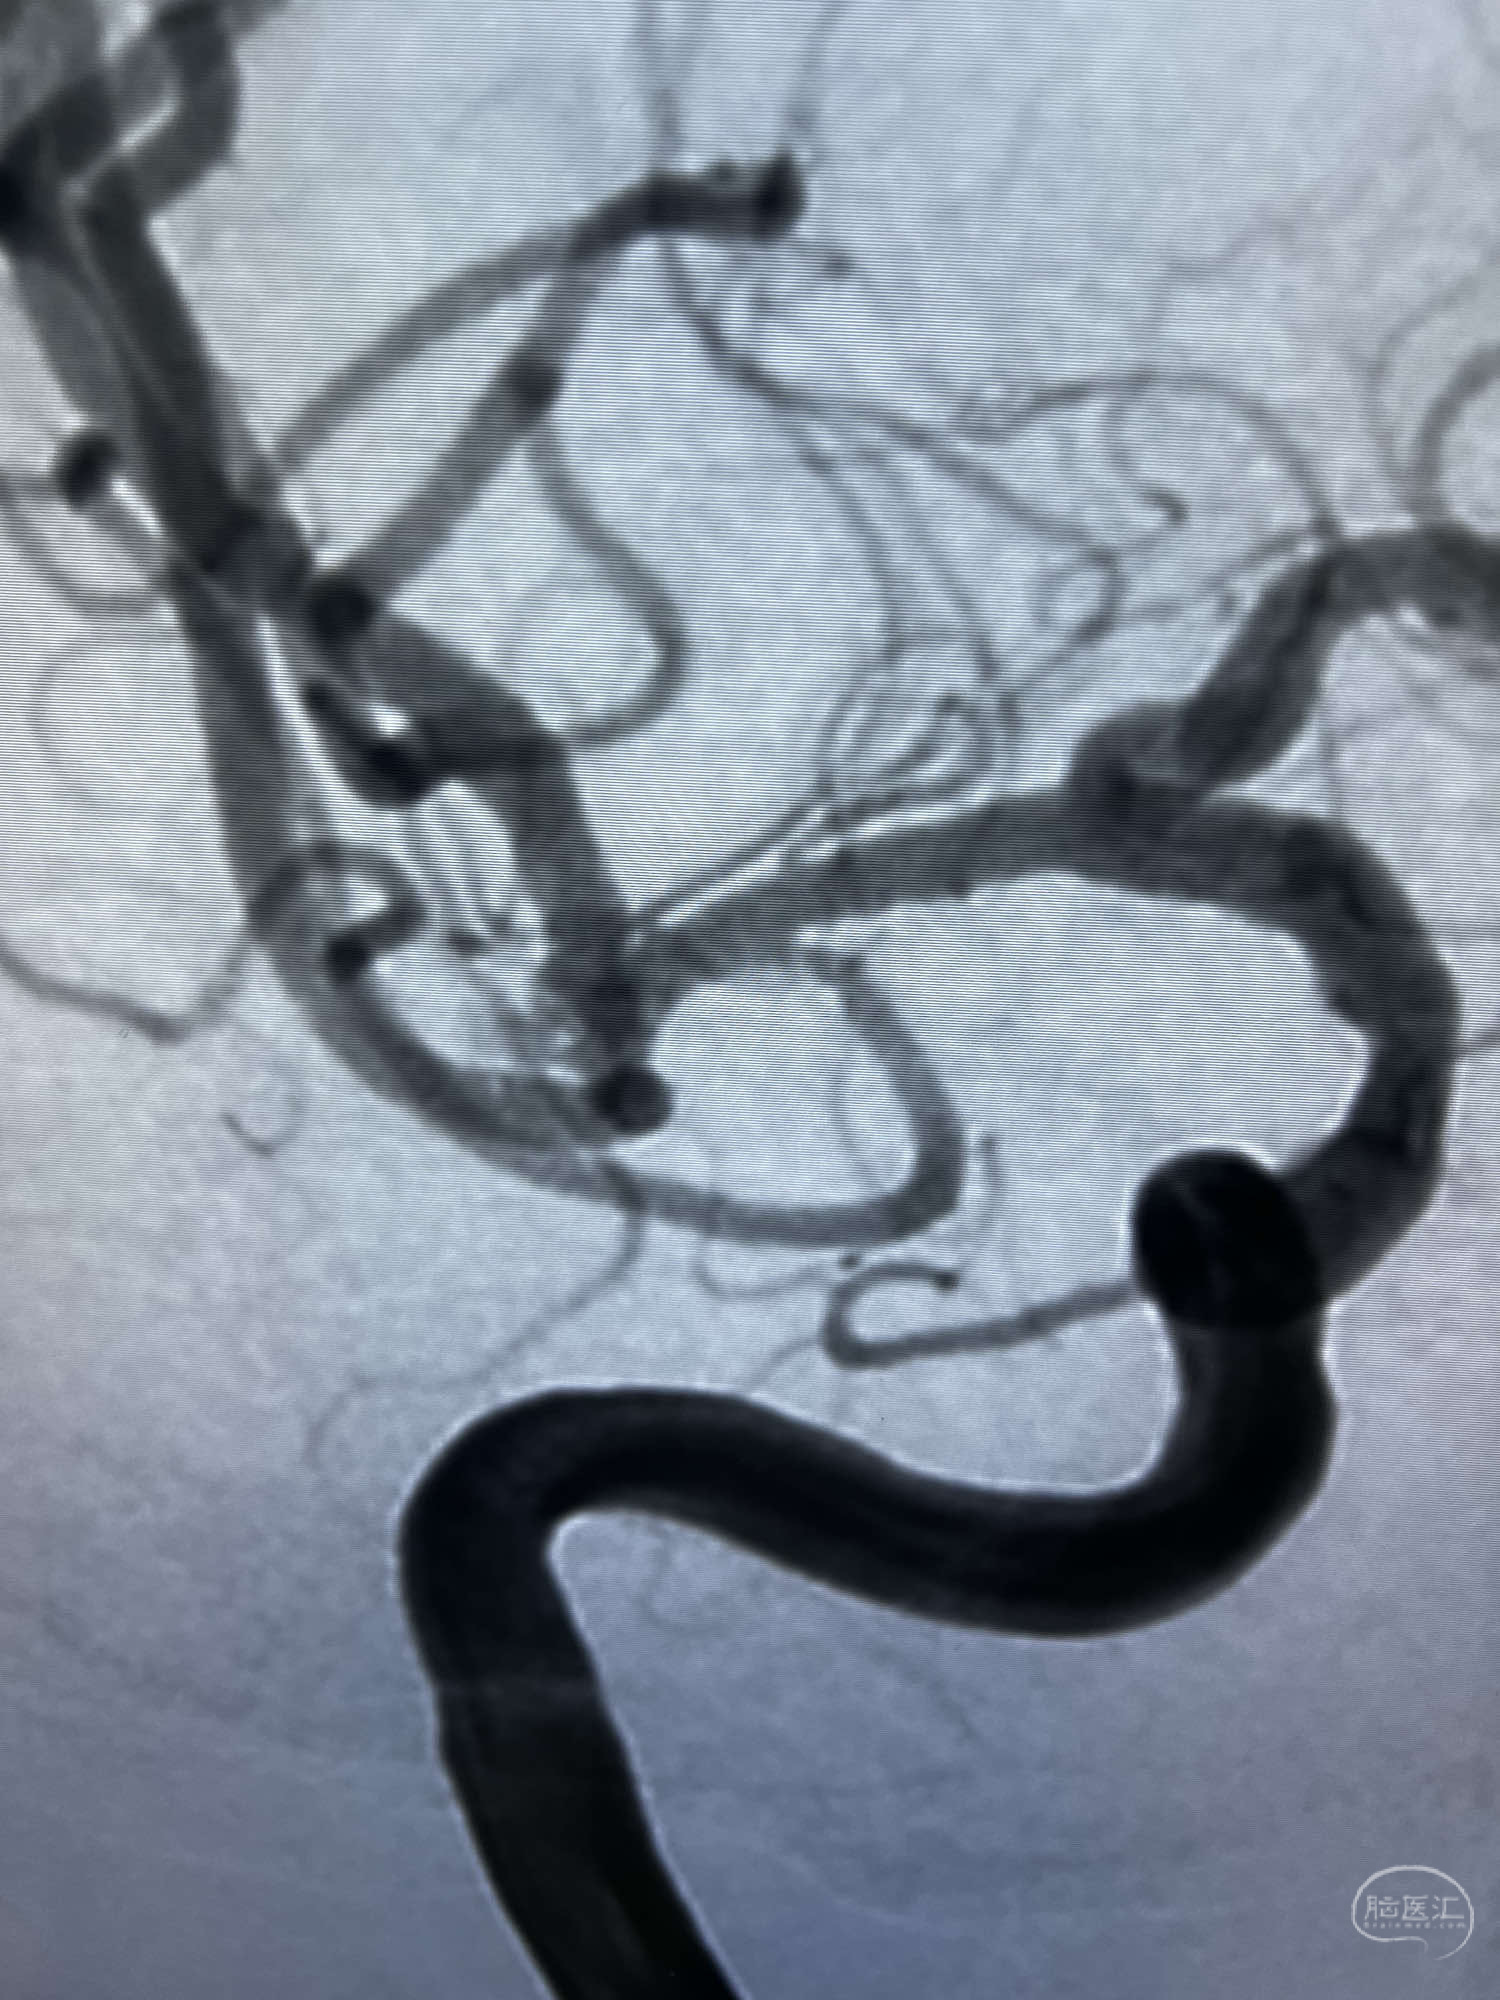

患者:LXS,M53Y,以“间断头晕头痛1周”为主诉入院,既往有高血压病及长期吸烟史。在当地医院行头颅CT未见异常,头颅MRA示右侧大脑中动脉M1段末端动脉瘤,左侧颈内动脉闭塞,交通动脉开放。

DSA示:左侧颈内动脉眼动脉段以远闭塞,后交通动脉开放,椎基底动脉通过后交通动脉代偿左侧大脑中动脉区域,右侧发出双侧大脑前动脉,右侧大脑中动脉M1末端宽颈动脉瘤,大小约4.3mmx4.6mm。

6F Neuromax➕6F115cm 心玮中间导管建立路径,sychro14微导丝➕VIA21超选至动脉瘤体内近中部,WEB5mmx3mm植入动脉瘤。

WEB瘤内扰流装置5mmx3mm经过“种子、萌芽、开花”三个阶段,打开后良好贴壁,动脉瘤内血液滞留,载瘤动脉通畅。WEB一步到位,通过瘤内扰流的方式起到栓塞动脉瘤的作用,避免了应用支架保护分支血管,简化了操作步骤,降低了术中血栓及出血的风险。